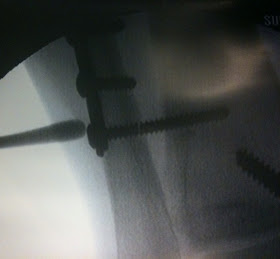

Pretty Princess had her surgery to remove the one screw that the doctor said had to come out...however...our sweet little princess had been spending too much time out of her boot and broke the screw so we will most likely be back here again in December to go after the remainder of the screw and remove more of the hardware if she is having trouble with it. (From the looks of the xray, she will be back.)

Check out the broken screw! The doctor said he usually only sees this happen in great big heavy guys! Guess that puts our petite Pretty Princess in an elite group! Move over big guys and watch out for the little lady!!

Here is what is left of the screw that may very well require removal later. Hmmmm.